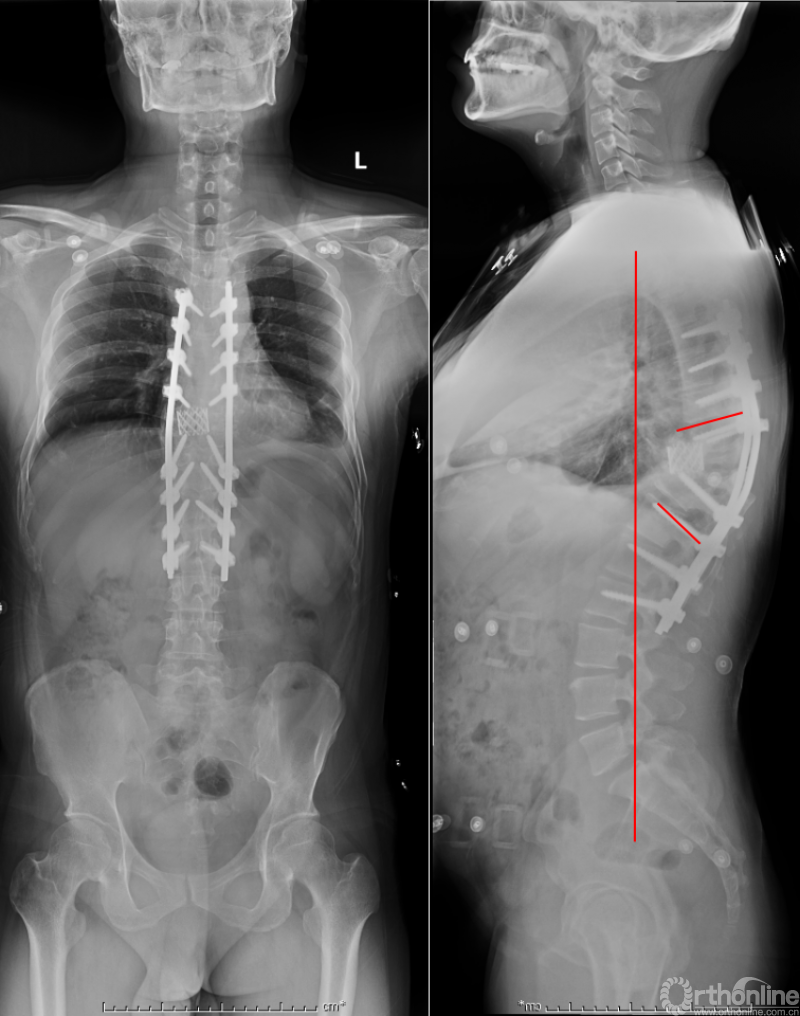

众所周知,脊椎结核后突畸形是结核病严重的后遗症之一。不仅影响患者外表仪容和心理,还可能出现晚发病灶造成截瘫。30多岁的小李就是一位脊柱结核后造成后凸畸形伴截瘫的患者,其畸形角度高达90度。针对此类患者的治疗大多就是截骨矫形,手术创伤大不说,椎体切除后造成的脊柱失稳等一系列后遗症也是令医生和患者担忧的。为解决临床上的这类问题,丁文元教授对传统的PVCR截骨技术进行了简化和改良,即后路单侧截骨部分椎体切除固定矫形术(UPVCR)入路,该技术采用后方单侧截骨,切除部分椎体、相邻椎间盘大部,保留对侧椎弓根及部分椎体,重建置入钛网支撑。随后,丁文元教授通过UPVCR技术对小李实施了手术,经过家人悉心地照顾,小李术后肌力恢复的良好,很快就出院了。三个月复查时竟是自己走路来的,临床疗效让患者及家人很是满意。

患者术前资料

患者术后资料

丁文元教授介绍说,UPVCR技术的优势在于手术操作简单,易于掌握,学习曲线短,手术时间短,出血少,神经并发症少;临床应用时极少发生断钉、断棒、不融合的现象,术中保留了良好的血运、植骨床,提供骨生长环境,保证部分骨支撑,术后极少发生矫正丢失,临床效果肯定。